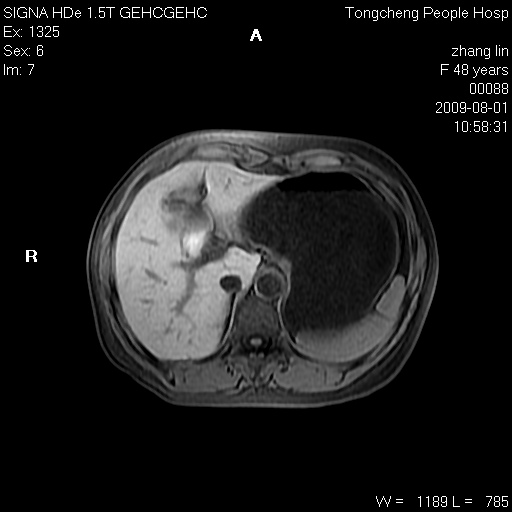

女,48岁。健康体检,彩超发现右肾占位性病变。平素健康。

临床诊断:右肾占位性病变,性质待定(囊肿?肿瘤?)。

上中腹部mr平扫+增强扫描,图像如下:

右肾上极见一类圆形病灶,t1wi呈等信号t2wi呈等高混杂信号,三期增强无强化,边界清---考虑囊肿出血。

同反相位均表现为等信号,病变无强化,考虑含蛋白的囊肿可能,弥散加权相或许有些帮助,